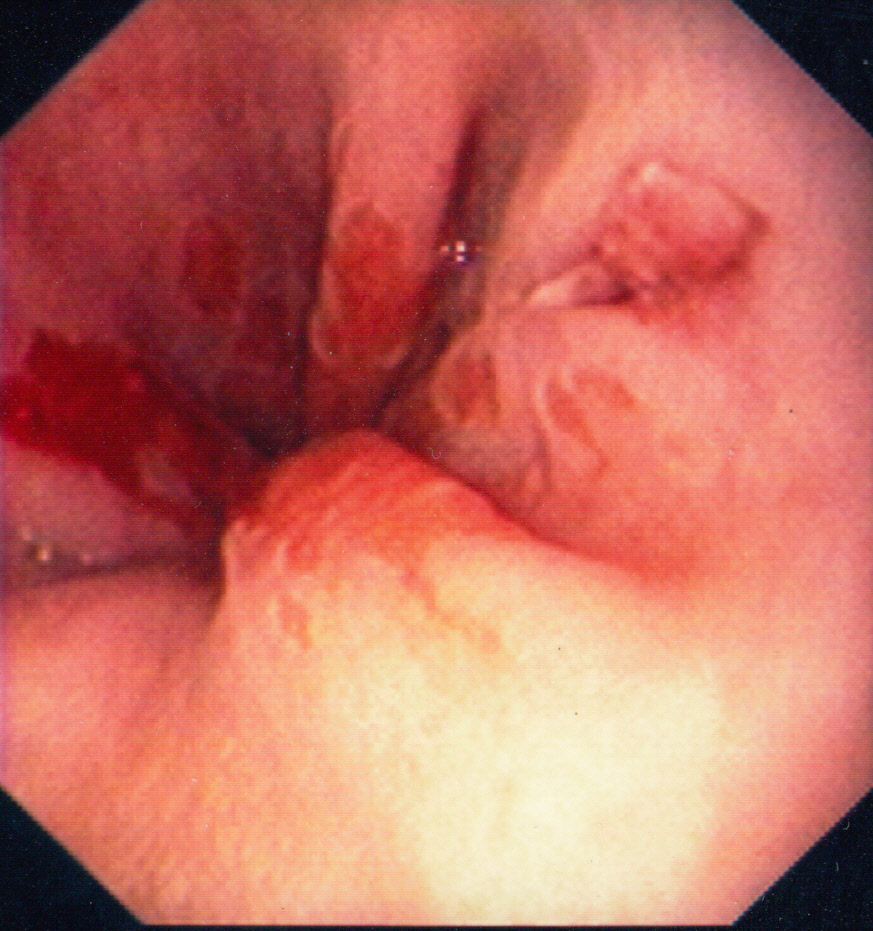

Mallory Weiss-tear

Mallory–Weiss syndrome or gastro-esophageal laceration syndrome refers to bleeding from a laceration in the mucosa at the junction of the stomach and esophagus. This is usually caused by severe vomiting because of alcoholism or bulimia,[1] but can be caused by any conditions which causes violent vomiting and retching such as food poisoning. The syndrome presents with hematemesis. The laceration is sometimes referred to as a Mallory-Weiss tear. (Source: Wikipedia)